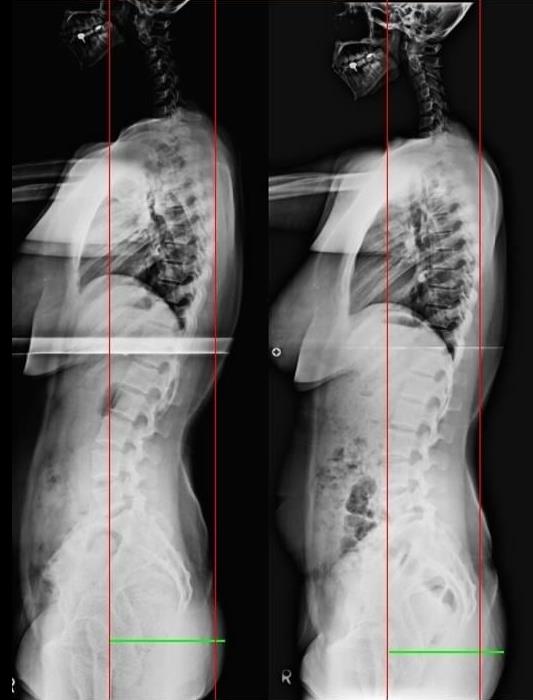

The following x-ray is of a patient who was treated for discomfort in the temporomandibular joint, who underwent short-term mcb splint treatment.

Until now, the deviation of patients who visited the hospital has always been the same pattern.

The right shoulder is rotating backward, and the left pelvis is rotating backwards.

In this movement, when the mcb splint is installed, the shoulder that was narrowed forward is stretched backward, and the right shoulder that moved backward moves forward.

And the left pelvis, which was moving backwards, begins to move forward.

At the same time, the spine moves straight as all the muscles move upwards instead of downwards.

These movements are consistent with the direction of deflection in scoliosis.